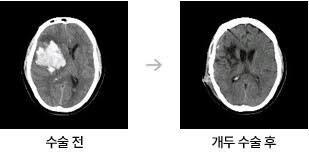

뇌출혈 수술은 뇌혈관이 파열돼 뇌 안에 피가 고인 상태를 제거하거나 압박을 완화하는 수술로, 이후 **의식회복 여부는 환자 예후를 결정하는 핵심 요소**입니다. 회복은 개인의 상태, 출혈 부위와 범위, 나이, 기저질환 등에 따라 크게 차이가 있으며, 적절한 치료와 재활, 가족의 지지가 매우 중요합니다.

- 출혈의 크기와 위치: 뇌간·기저핵 출혈은 의식회복 가능성이 낮음